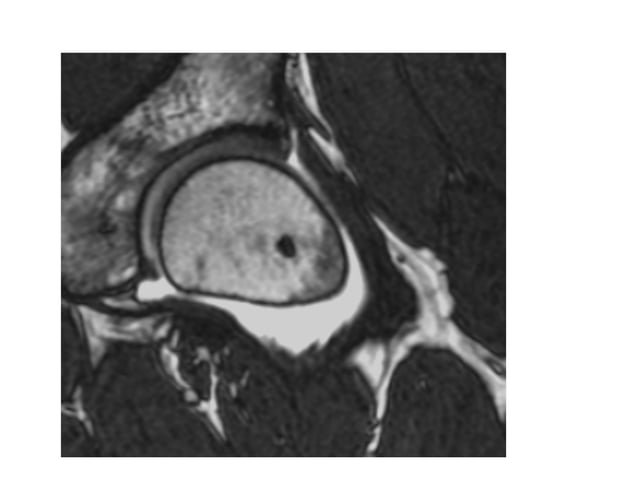

- MRI-scan: De gouden standaard! Een MRI kan de cyste haarfijn in beeld brengen, inclusief de grootte en de exacte locatie.